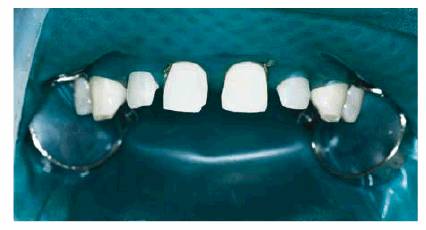

DIASTEMA CAUSED BY TEETH TOO SMALL

PROBLEM: This 28-year-old male store manager was so self-conscious about

smiling that he adopted a more "serious" demeanor (Figure 23-9A) so that he would not have to

smile.

Figure 23-9A: This 28-year-old man presented with multiple diastemas and teeth too small for his facial structure.

TREATMENT: Esthetic analysis of the patient's smile, using a dental dial

caliper, revealed teeth that were too small to be proportionate. Thus, even if

orthodontics were chosen, the outcome would still result in a disproportionate

smile. Therefore, the patient chose composite resin bonding as both an economic

and immediate solution.

First, the shade selection was determined by testing different materials

directly on the teeth. Once this was completed, a rubber dam was applied to

maintain isolation during the procedures (Figure 23-9B). Next, the right central incisor

was bonded to the predetermined mesiodistal width, measured again, and reduced

slightly with a series of SoFlex discs (3M ESPE, St. Paul, MN) to exactly two

of the spaces to be filled in (Figure 23-9C). Then the right central incisor

was wrapped with a 5/10,000-inch thickness shim stock (Artus), held in place

with an alligator clip, and the left central incisor was restored (Figure 23-9D

Figure 23-9B: A rubber dam was placed to maintain isolation during a multiple bonding procedure.

Figure 23-9C: The teeth were measured, sized, and proportionally bonded one by one.

Figure 23-9D: After bonding the right central incisor, composite resin was placed on the left central incisor to close the space.

Finishing procedures included the ET (Brasseler,

Figure 23-9E: The final results from bonding six anterior teeth.

Figure 23-9F: One year later, the smile remained balanced and proportional for this patient.

RESULT: This balanced smile, shown 1 year

later (see Figure 23-9F), is the product of reproportioning

six teeth that were too small for the patient. Although orthodontics alone

could have been used to close the spaces, the end result would not be as

satisfying, both functionally and esthetically.